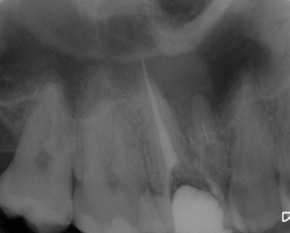

Patient N.M. wünscht eine Drittmeinung, zwischenzeitlich hatte er bereits einen zweiten Zahnarzt konsultiert. Dieser bestätigte eine insuffiziente Wurzelfüllung und vermutete eine Instrumentenfraktur im mb1 (Abb. 1).

Röntgenbefund

Mittels Röntgenaufnahme lässt sich ein frakturiertes Instrument in mb1 vermuten. Des Weiteren scheint es, als sei der distale Wurzelkanal sowie der mb2 nicht abgefüllt worden, was sich zu einem späteren Zeitpunkt der Behandlung bestätigen sollte. Der Patient wurde vom vorbehandelnden Zahnarzt über die Fraktur nicht aufgeklärt.